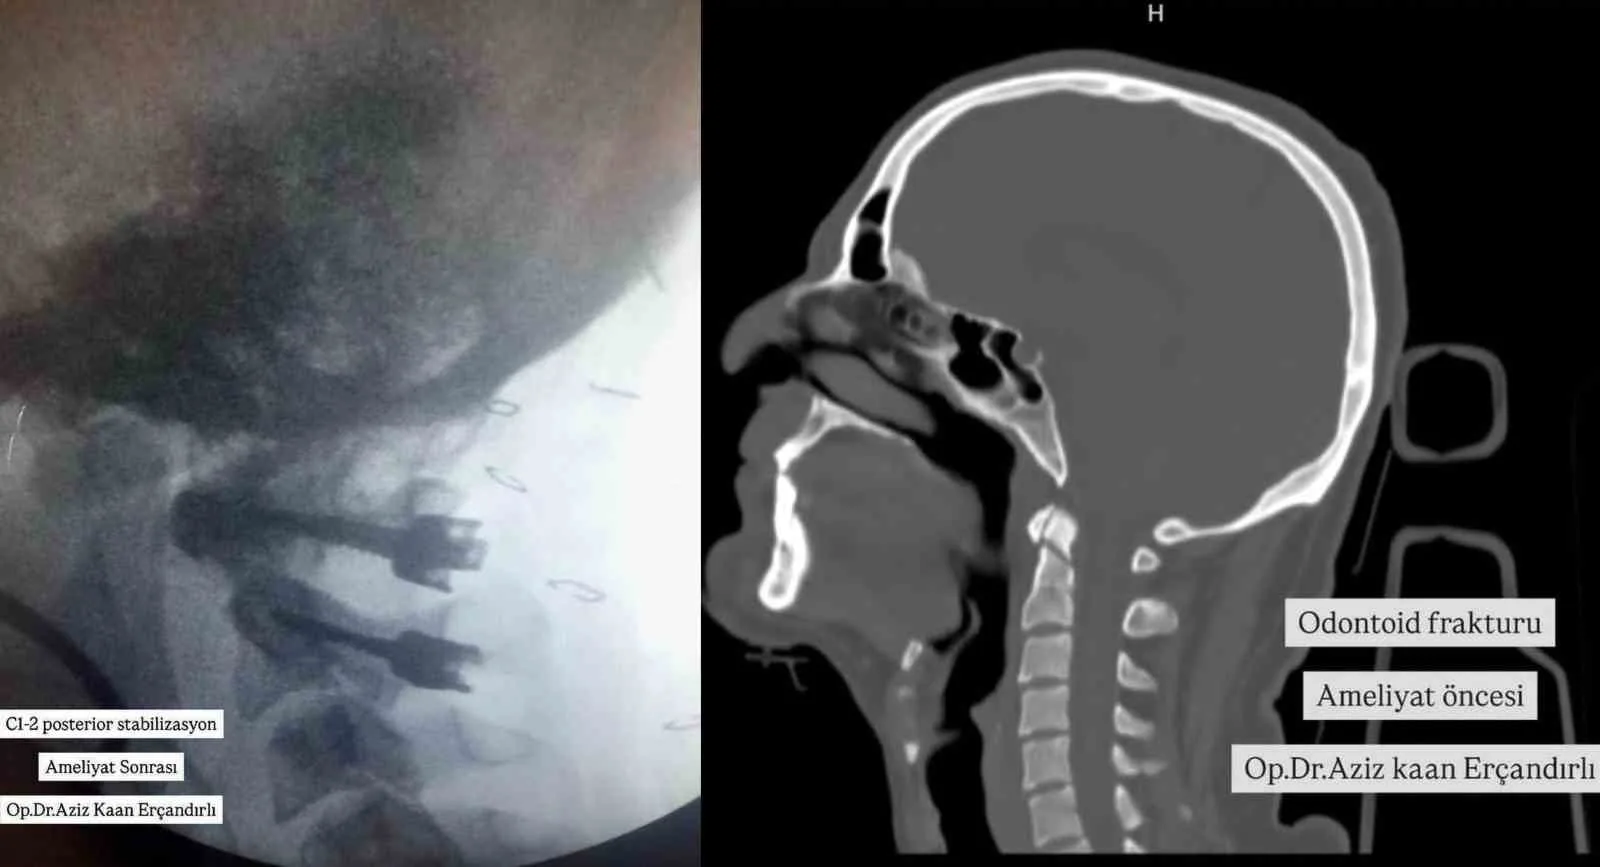

Yüksekten düşme sonrası vücudunda kırıklar oluşan bir hastaya Bayburt Devlet Hastanesinde ilk kez C1-2 posterior stabilizasyon başarıyla yapıldı.

Konuya ilişkin hastanenin sosyal medya hesabı üzerinden yapılan açıklamada, “Bu hastamızda yüksekten düşme sonrası odontoid tip 2 kırığı olması üzerine Bayburt’ta ilk defa C1-2 posterior stabilizasyon yapıldı. Odontoid çıkıntı, kafatabanı ve boyun bileşkesi geniş hareket becerisi açısından önemli bir parçasıdır. Böylesi geniş hareket aralığı ile birlikte stabilitenin idamesi de ayrı bir özellik taşımaktadır. Bu yüzden odontoid kırıkları servikal kırıklar içinde önemli bir yere sahiptir. Çoğunluğu yüksek enerjili travmalarla oluşur ve sıklıkla zorlayıcı fleksiyon ve/veya ekstansiyon hareketleri sonucu oluşmaktadır. Boyun Kırığı Ameliyatı Beyin ve Sinir Cerrahisi Uzmanımız Aziz Kaan Erçandırlı tarafından başarılı bir şekilde gerçekleştirilmiştir.” ifadelerine yer verildi.

YÜKSEKTEN DÜŞME SONRASI VÜCUDUNDA KIRIKLAR OLUŞAN BİR HASTAYA BAYBURT DEVLET HASTANESİNDE İLK KEZ C1-2 POSTERİOR STABİLİZASYON BAŞARIYLA YAPILDI